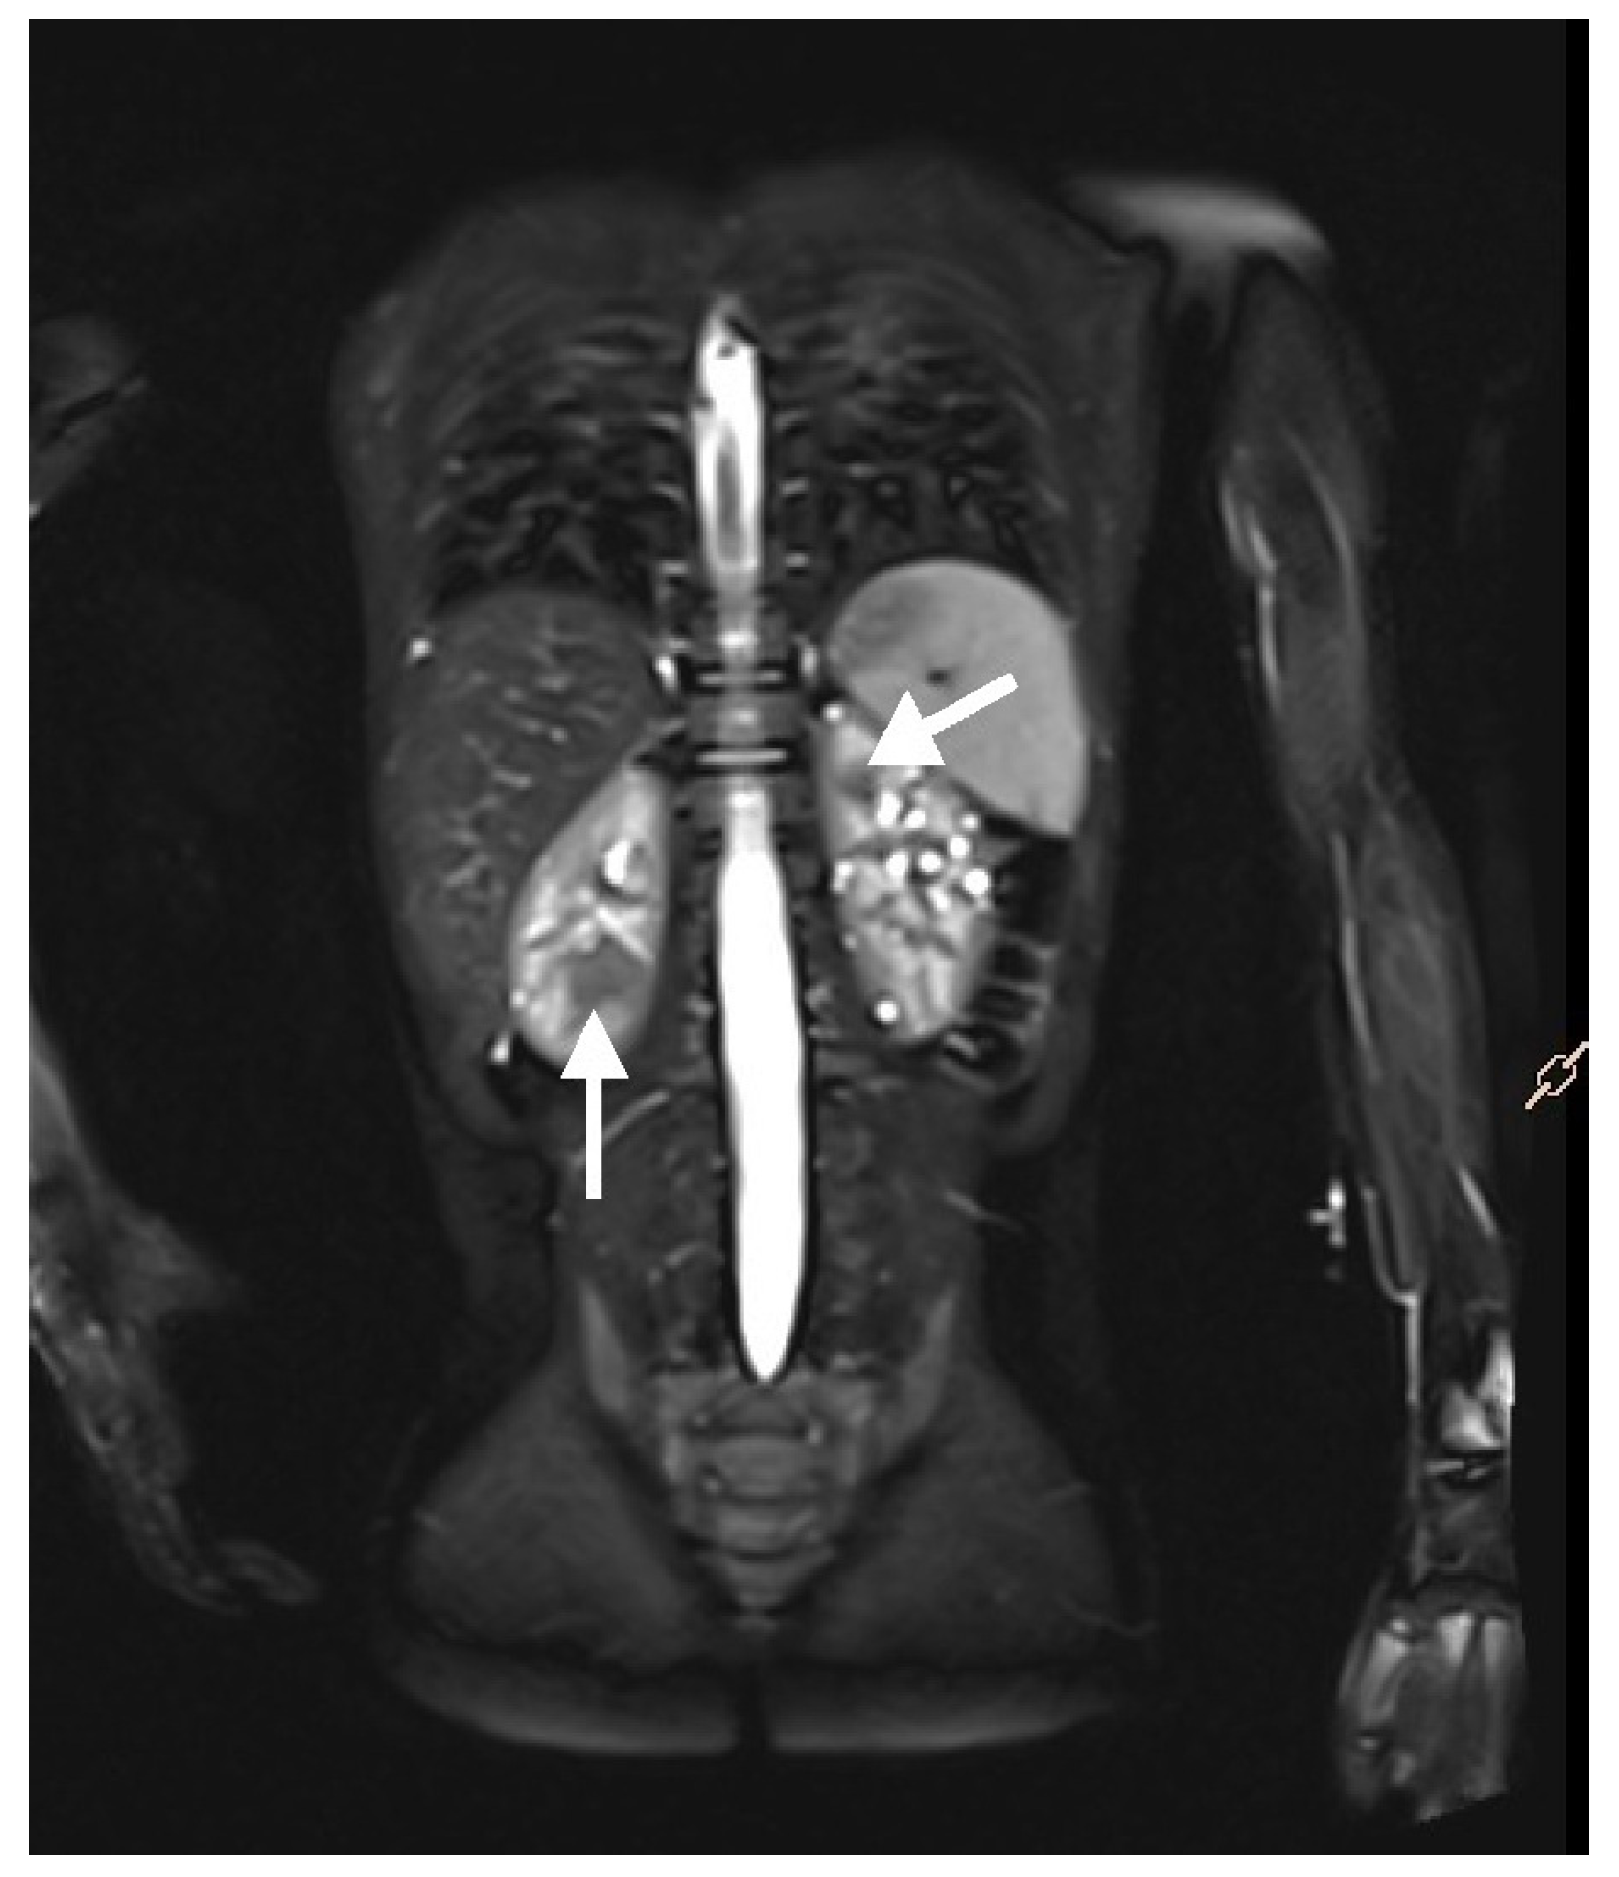

Magnetic resonance imaging (MRI) of the abdomen (Figure 5) and brain is the recommended imaging technique to diagnose and follow-up TSC-related kidney lesions. It remains the preferred method for evaluating AMLs, as 25–30% of them are fat-poor and are frequently overlooked in standard abdominal ultrasound examinations [6,49,50]. Additionally, MRI is highly effective in detecting other common abdominal abnormalities associated with TSC, such as renal cysts, aortic aneurysms, extrarenal hamartomas in the liver, and neuroendocrine tumors in the pancreas and other abdominal organs [51]. All individuals suspected of having TSC, should undergo MRI assessment of the brain to evaluate for cortical and subcortical tubers, subependymal nodules (SENs), neuronal migrational defects, and subependymal giant cell astrocytomas (SEGAs) [6].

Figure 5. An MRI with contrast of a 5-year-old boy. Multiple solid focal lesions in both kidneys—atypical angiomyolipomas (arrows). Additionally, numerous small cysts within the parenchyma of both kidneys.